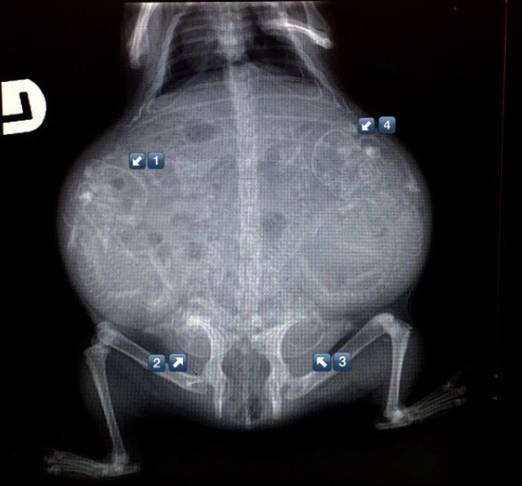

16. 蜥蜴。

有看到3个蜥蜴宝宝吗?